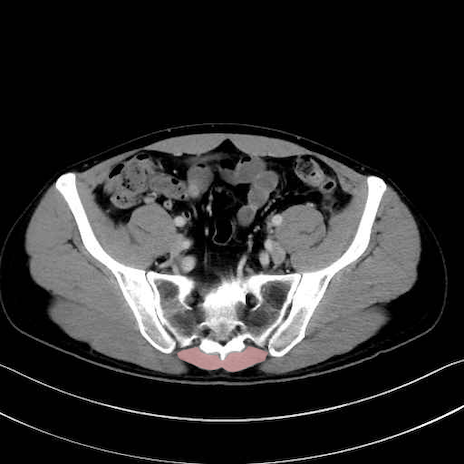

肛門挙筋 (Levator ani)